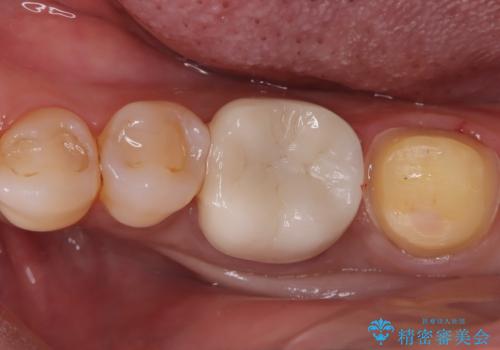

- 左下の奥歯の詰め物が取れたとのことで来院されました。診察したところ、左下6番には噛む力による複数のヒビ(クラック)が確認され、歯の寿命を考えると将来的な破折のリスクがある状態でした。

噛む力が強い方に多く見られる症状であり、これ以上の破折を防ぐためには補綴による補強が必要と判断しました。治療計画としては、左下6・7番ともに全体を覆うセラミッククラウンで補強し、咬合力に耐えられる状態に回復させる方針を立てました。また、清掃がしづらく炎症の原因にもなっていた親知らずについても、全体の予後を考えて抜歯することとしました。

まず左下6番のヒビや弱くなった部分を除去し、セラミッククラウンが適切に装着できる形に整えました。隣接する7番についても同様に支台形成を行い、両方の歯を連続して補強する形としました。クラウンは、見た目の自然さと耐久性を兼ね備えたセラミックを選択し、咬合圧に配慮したデザインと高さ調整を丁寧に行いました。